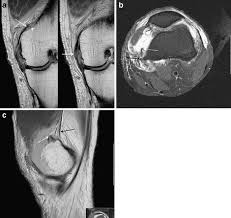

33 M 7 Metaphyseal Avulsion

33 M 7 Metaphyseal Avulsion from resources.aofoundation.org